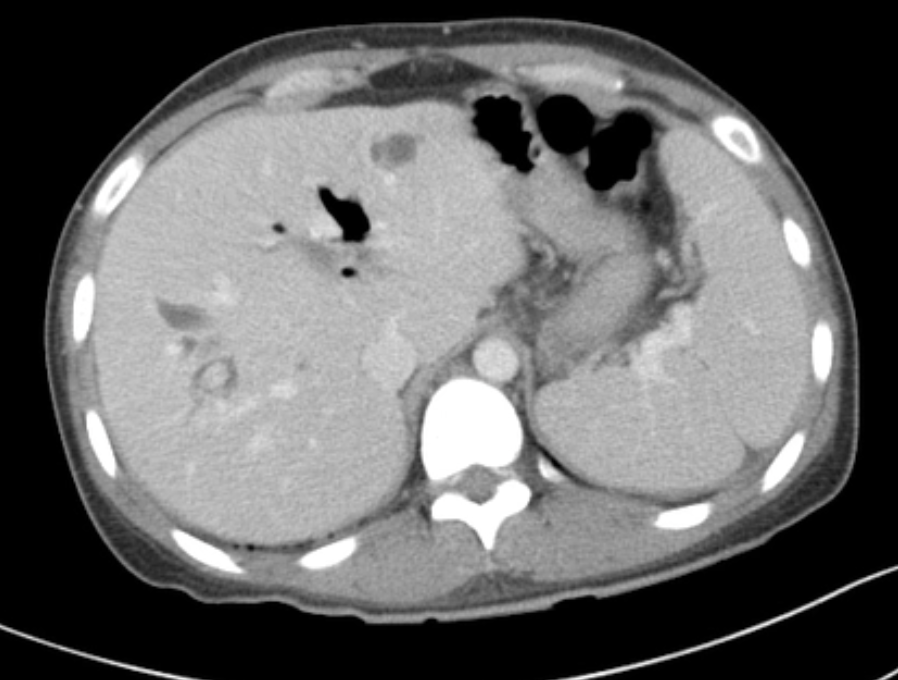

Dilated ducts Dx

Dx?

DDx cystic hepatic lesion

Choledochal cysts

Dx: type 4A choledochal cyst.